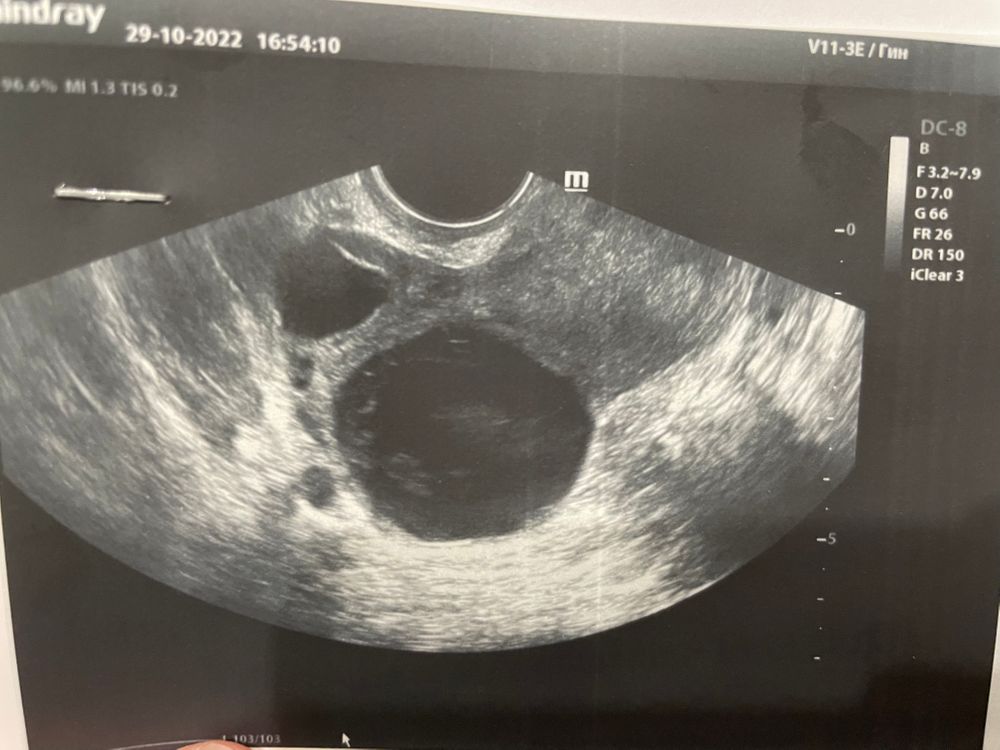

Желтое ли тело на снимке узи? Которое поменьше..Большое пишут кистой, неизвестно какой. Не совсем доверяю врачу узи. Подскажите)